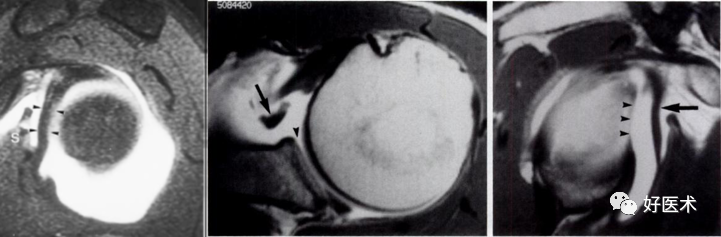

1.Bankart lesion

盂肱下韧带和前盂唇(前下盂唇韧带复合体)从关节盂边缘撕脱,伴肩胛骨骨膜的撕裂。首次损伤后不恰当愈合可导致反复肩关节不稳。

2.Bony Bankart lesion

前下盂唇韧带复合体从关节盂边缘撕脱,伴继发于前关节脱位的肩胛盂骨性骨折。

3.Perthes lesion

Bankart lesion的变异:前下盂唇韧带复合体从关节盂边缘脱离,但骨膜完整且向前内侧剥脱,因此盂唇可在正常解剖位置。

4.前盂唇韧带骨膜袖撕脱

多见于反复脱位的患者。类似于Bankart 损伤,但其肩胛骨前骨膜保持完整,MR 关节造影显示对比剂出现于盂唇与肩胛骨关节盂之间,而骨膜完整连于肩胛盂 。

需与关节盂唇的变异鉴别。